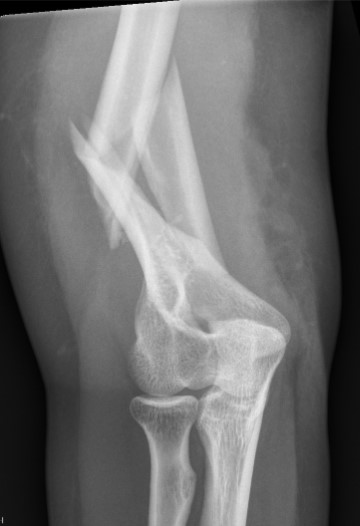

Displaced Humeral Fracture APDisplaced Humeral Fracture Lateral

Multi-trauma

Floating elbow

Segmental fracture

Proximal fracture

Displaced Holstein Lewis with radial nerve palsy

Pathological fracture - won't heal

Bilateral humeral fractures

Obese (very difficult to splint)

Brachial plexus injury - allows early rehab

Humeral Fracture SegmentalHumeral Plate LateralHumeral Plate Long AP

Segmental fracture ORIF